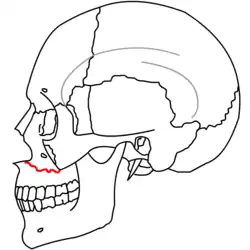

| Le Fort II fractures | |

At the beginning of the 20th century, René Le Fort mapped typical locations for facial fractures; these are now known as Le Fort I, II, and III fractures (right).[7] Le Fort I fractures, also called Guérin or horizontal maxillary fractures,[14] involve the maxilla, separating it from the palate.[15] Le Fort II fractures, also called pyramidal fractures of the maxilla,[16] cross the nasal bones and the orbital rim.[15] Le Fort III fractures, also called craniofacial disjunction and transverse facial fractures,[17] cross the front of the maxilla and involve the lacrimal bone, the lamina papyracea, and the orbital floor, and often involve the ethmoid bone,[15] are the most serious.[18] Le Fort fractures, which account for 10–20% of facial fractures, are often associated with other serious injuries.[15] Le Fort made his classifications based on work with cadaver skulls, and the classification system has been criticized as imprecise and simplistic since most midface fractures involve a combination of Le Fort fractures.[15] Although most facial fractures do not follow the patterns described by Le Fort precisely, the system is still used to categorize injuries.[5]